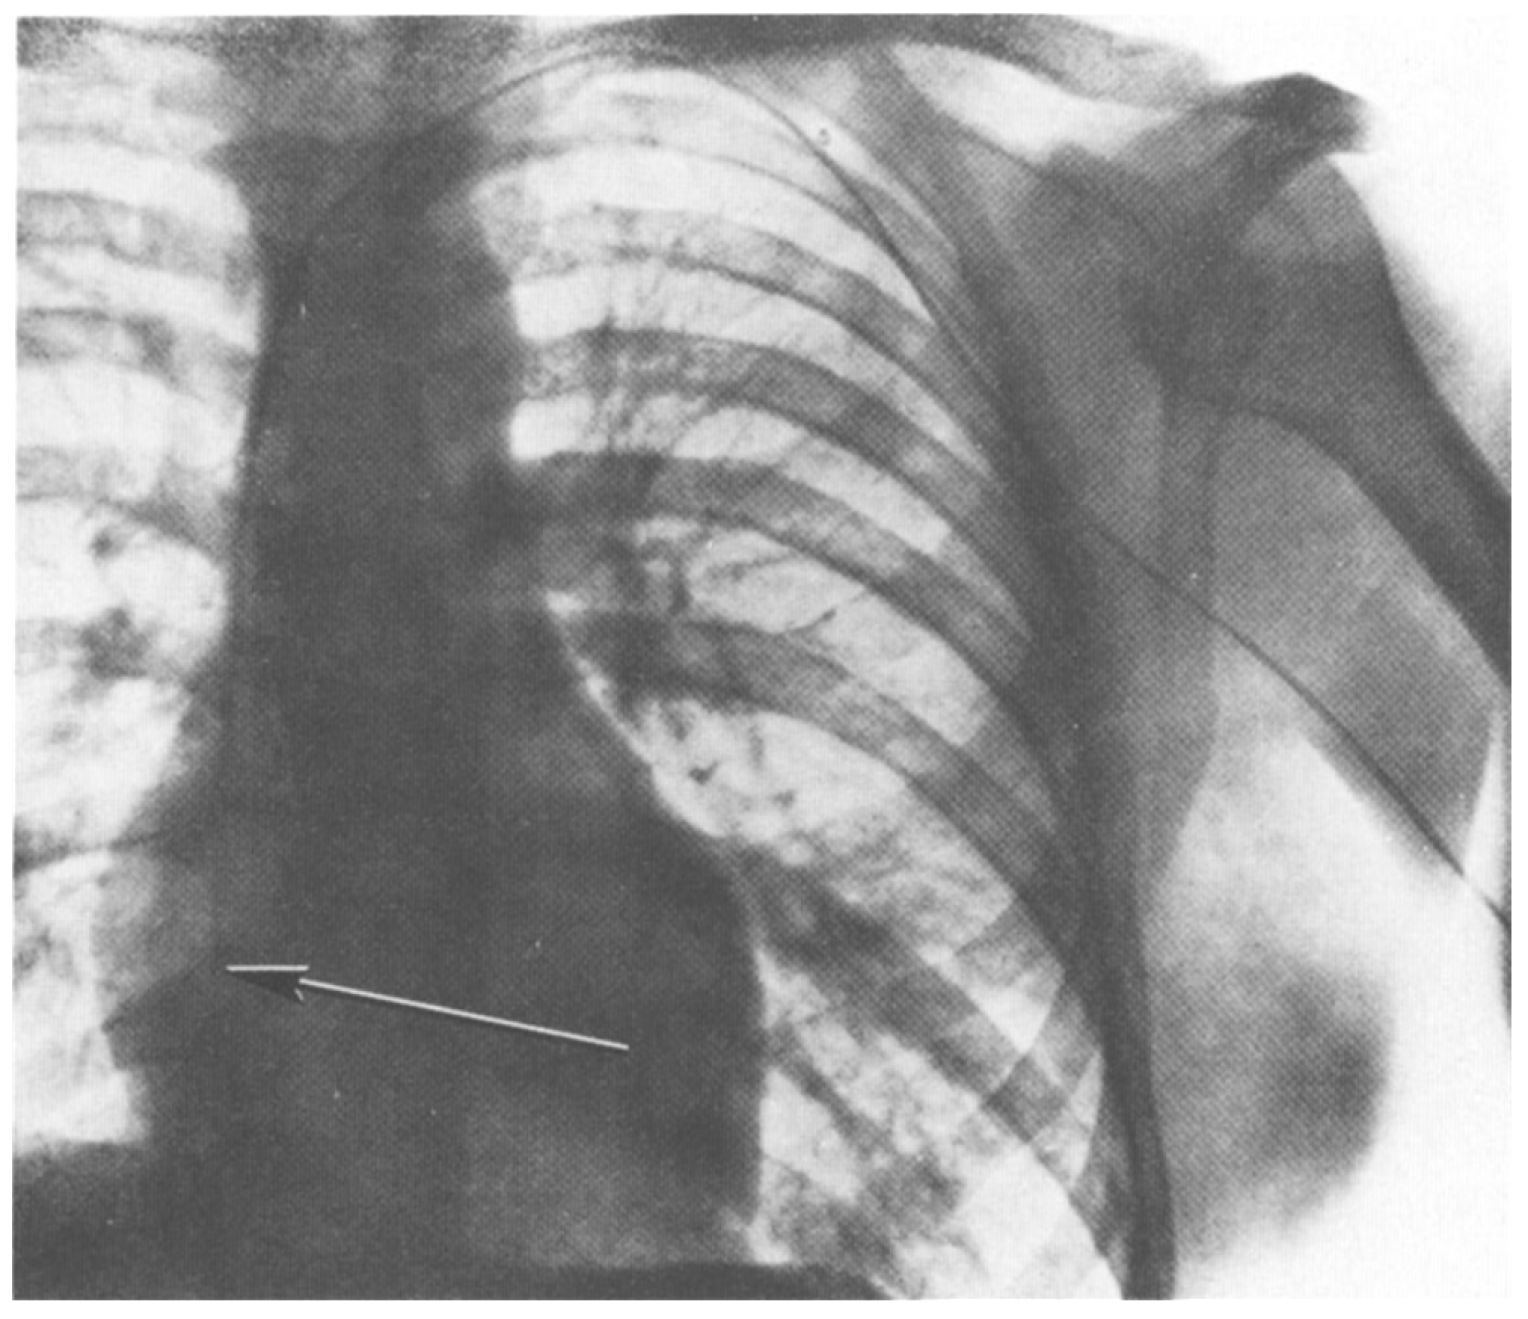

In 1929 at the Auguste-Viktoria Hospital in Eberswalde, Germany, Dr. Werner Forssmann fed a catheter through his arm vein all the way to his heart. He recorded this feat on x-ray (using an x-ray machine one floor above his own lab; see Figure 1). The x-ray shown in Figure 1 documented Forssman’s self-experiment and was published that year (Forssmann, 1929). This daring work, for which Forssmann was eventually awarded the Nobel Prize in Physiology or Medicine, ushered in the field of cardiac catheterization. The story of Forssmann’s experiment is retold in a recent article on overregulation (Morris, 2023) and in greater detail in a book on self-experimentation (Altman, 1998).

Figure 1.

X-ray of W. Forssmann’s torso after self-catheterization. Catheter shown on x-ray from original publication (Forssmann, 1929). From the original figure legend, “the catheter passes directly inward from the left arm, under the clavicle at the chest wall, and makes a downward bend at the place of junction with the jugular vein, lying near the margin of the great-vessel shadow and the shadow of the spine, and reaching as far as the right atrium. On another passage, the catheter did not reach any further than this. “I watched carefully for any other effects, or signs of irritation of the cardiac mechanism, but could not identify any. In our institution there is a considerable distance between the operating rooms and the x-ray unit. To go from one to the other I had to climb staircases on foot and return, while the probe was lying within my heart, but I was not aware of any unpleasantness. Passage and removal of the catheter were entirely painless, accompanied only by the above-mentioned sensations. Later on, I could find no sequelae to the procedure…” (Forssmann translated by Meyer, 1990).